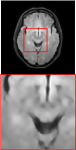

Figure 5 provides the qualitative comparison of the various methods on the four datasets at a scale of 4. The top, second, third, and bottom rows are the SR results under the FastMRI, clinical brain, clinical tumor and clinical pelvic datasets, respectively. The red boxes indicate the zoom-in region of complicated anatomical structures along with their corresponding error maps. Note that the brighter textures in the error maps, the lower the quality of the reconstructed images. As can be seen, compared to methods based on Transformers and CNNs, diffusion-based methods like DisC-Diff and DiffMSR (Ours) are capable of reconstructing high-realistic images with promising reconstruction metric scores (PSNR and SSIM). Nevertheless, while DisC-Diff can reconstruct high-precision MR images, it does not preserve the structure present in the original HR images, introducing some additional information that can affect medical diagnosis. In contrast, our method combines DM and PLWformer, which can preserve the original image’s structure while restoring high-frequency information.

In this section, we present more visual qualitative comparisons. Figures 8, 9, 10, and 11 show the reconstruction results of each method in FastMRI, clinical brain, clinical tumor, and clinical pelvic, respectively. As can be seen, although DisC-Diff can reconstruct MR images with high-frequency information, it fails to preserve the structure and content of the original Target HR image effectively, resulting in image distortion. In contrast, our proposed DiffMSR can restore high-frequency information while preserving the structure of the original HR image, indicating the effectiveness of the joint use of DM and PLWformer.